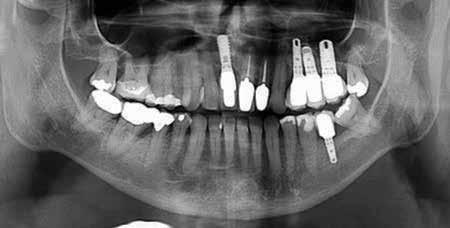

#13, #14 for ridge preservation. At a later date, three implant-supported crowns in close proximity were placed in these sites. Notably, the crowns were non-splinted. (Fig. 1).

In July 2021, the patient presented with mobile implants #12, #13 and #14 to his dental practitioner (Fig. 2). The implants were removed without bone grafting.

Fig. 1: May 2021. Panoramic radiograph shortly after placement of upper left #12, #13, #14.